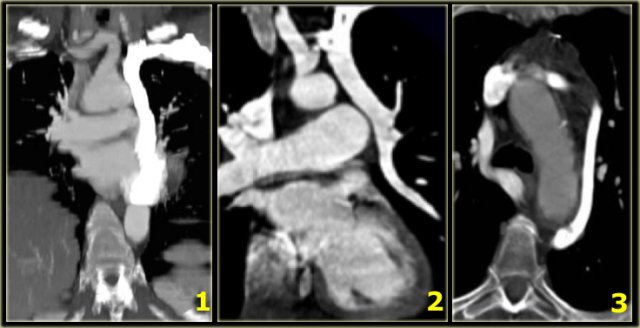

Mirror image aortic arch in patient operated for tetralogy of Fallot. Mirror image aortic arch in patient operated for tetralogy of Fallot.

On the left an adult who was operated in his childhood for a Tetralogy of Fallot (pulmonary stenosis, right ventricular hypertrophy, VSD, overriding aorta).

At surgery the VSD was patched and the pulmonary outflow tract was enlarged.

Notice that there is also a right arch.

In the United States there are now more than one million adults who have survived their congenital heart disease.

In the ER you will see these patients because they age and get chest pain like many adults do and so you will see these anomalies more frequently.